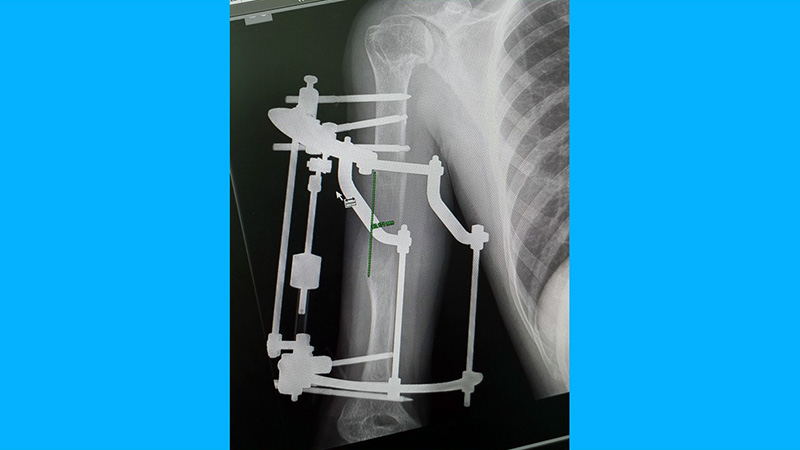

Con il team Kirienko, abbiamo eseguito con successo un’osteotomia dell’omero con applicazione di fissatore esterno tipo Ilizarov. Questo approccio ha permesso di ottenere un allungamento progressivo e controllato dell’osso.

Dopo la completa consolidazione del rigenerato osseo e la successiva rimozione del dispositivo, il paziente ha potuto riprendere le proprie attività senza alcuna alterazione della funzione, con un recupero ottimale sia dal punto di vista anatomico che funzionale.